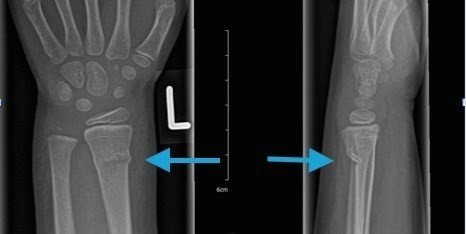

Accurate Diagnosis for Effective Fracture Care

Correct diagnosis is essential for successful fracture treatment. Ortho Plus Care uses detailed clinical evaluation and appropriate imaging to determine the type, location, and severity of fractures in children.

This diagnostic accuracy is a key factor behind the Best Children’s Fracture Treatment in Gurugram Sector 46. Early and precise identification allows doctors to choose the safest and most effective treatment approach for each child.